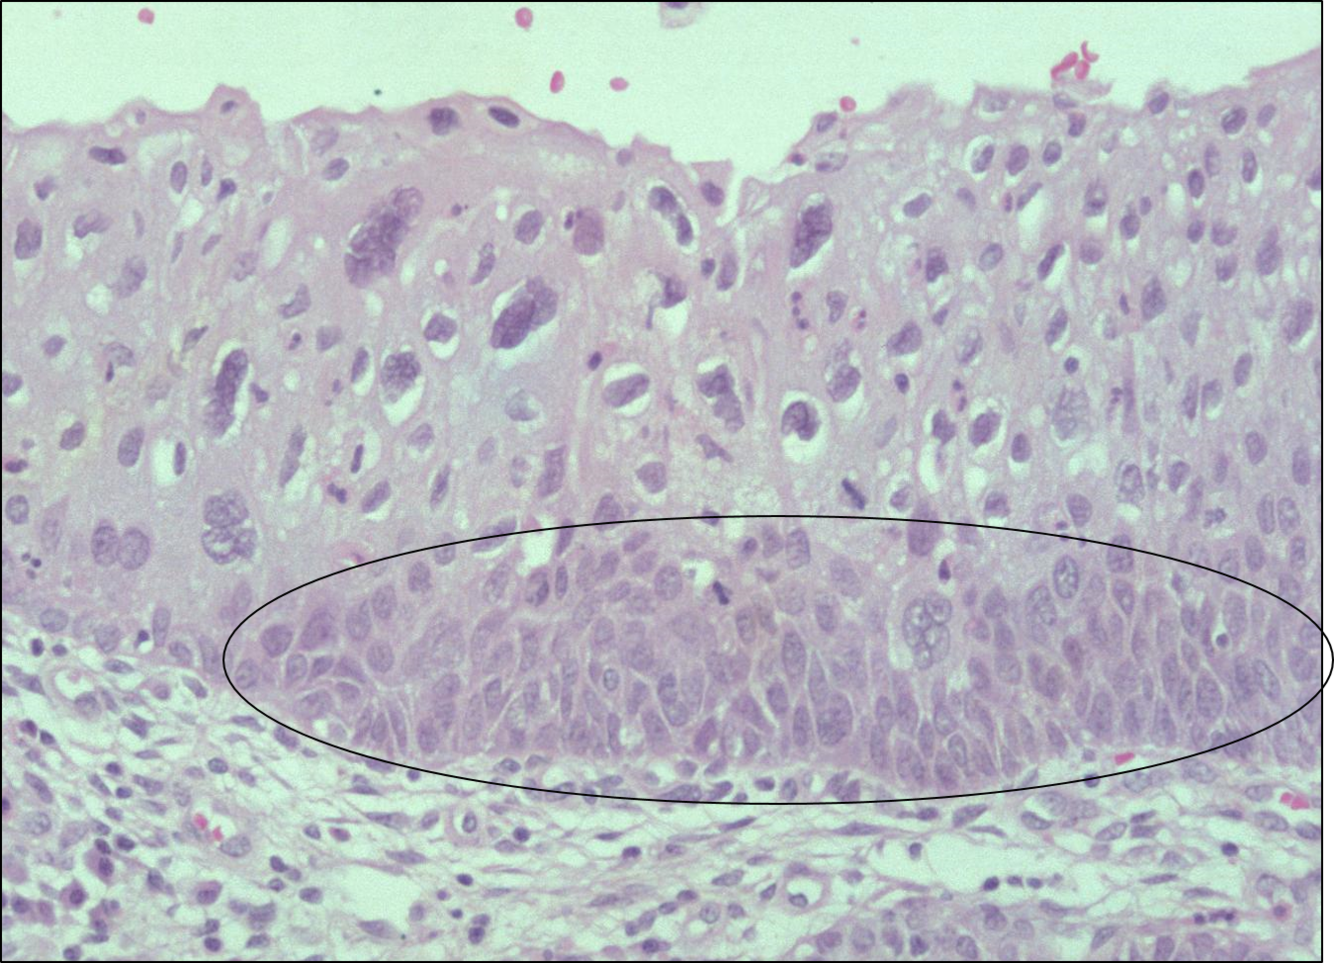

Appreicate this pic of HPV infection causing mild dyskaryosis (CIN 1)

Dyskaryosis = An abnormality of nuclei seen in exfoliated cells, often cells from the uterine cervix, in which the cytoplasm remains unchanged but the nuclei exhibit hyperchromatism, irregularity or enlargement, or an increase in number.

How is CIN graded ?

It is graded from 1 to 3 on the proportion of in thirds of the epithelium whcih is occupied by abnormal cells

CIN I - Basal 1/3 of epithelium occupied by abnormal cells:

CIN II - Abnormal cells extend to middle 1/3.

CIN III - Abnormal cells occupy full thickness of epithelium.

What classification of CIN is shown ?

CIN 1

Compare to the normal ectocervix its easier to see this way